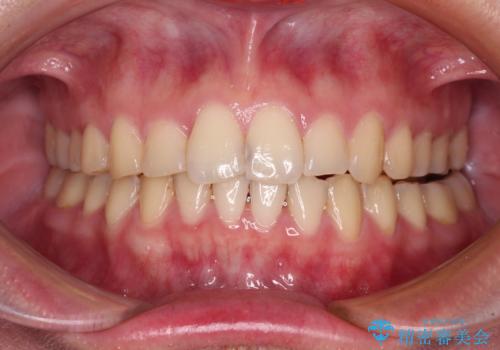

- 八重歯を気にして来院された高校生の患者様です。

ボディーコンタクトの激しい部活動を行っているため、補助装置とインビザラインを用いて、部活動を継続しながら治療を行うこととしました。

八重歯を効率よく改善するため、補助装置を使用して上顎の奥歯を後方に移動させました。

部活動をしながらでしたが、マウスピースをしっかりと装着してくださったので、1年半程度で終了することができました。